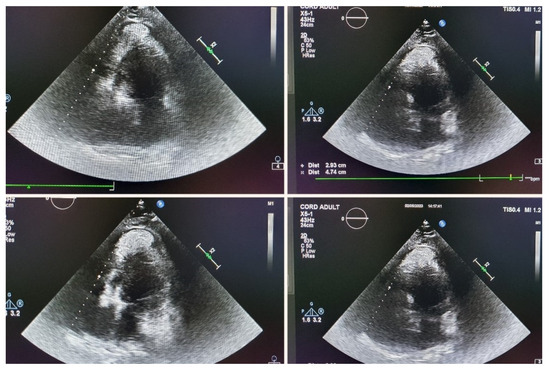

| 2 May 2023 | third emr: cardiac and colonic mass (+cns?) | nelarabine+cyclophosphamide+ etoposide |

| 2017 Baritussio [46,47] | 38 y.o. man | 9 months after allotransplantation by infiltration in the eyes, myocardium, and pericardium Flocytometric MO and CSF 0.09% T-lymphoblastic lymphocytes were highlighted. He was treated with nelarabine PEV and intrathecal cytosar, with the resolution of the eye and heart tumor | T-ALL |